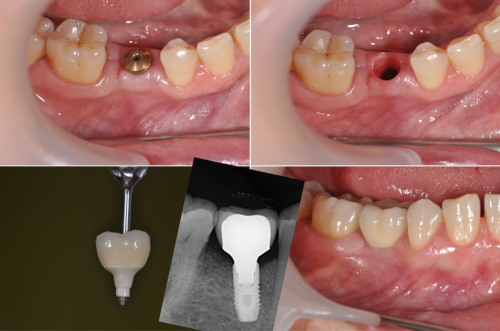

La pose implantaire consiste à positionner une vis biocompatible sur le ou les sites édentés. Cette « nouvelle racine » sera le support de votre nouvelle dent.

Nos implants sont de la marque EUROTEKNIKA (ETK), reconnue pour sa qualité et ses innovations dans le domaine des implants dentaires.

2. Pose de l’implant : Intervention sous anesthésie locale, réalisée dans un bloc opératoire dédié pour une sécurité maximale.

3. Cicatrisation : Phase d’intégration de l’implant à l’os.

4. Prise d’empreinte numérique : Permet de créer une couronne parfaitement ajustée.

5. Fixation de la couronne : La prothèse est fixée pour une mastication optimale et un rendu esthétique naturel.